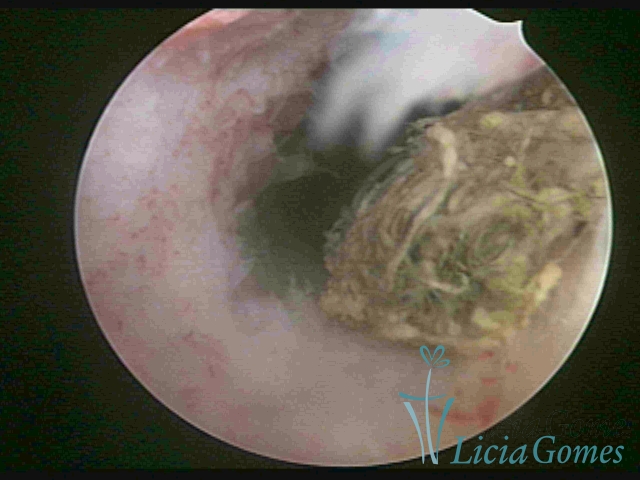

Uterine cavity with an old, folded IUD